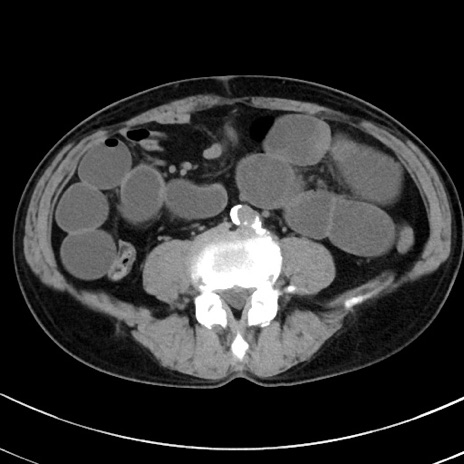

症例38(横断像)

【症例】70歳代 男性

【主訴】腹痛・嘔吐

【現病歴】昨晩より、嘔吐・腹痛あり。今朝になっても嘔吐あり。来院。

【既往歴】心臓バイパス手術、開腹胆摘、腸閉塞

【身体所見】BP 107/71mmHg、HR 116/min、腹部:平坦、軟、下腹部に軽度圧痛あり。反跳痛なし。

【データ】WBC 15100、CRP 0.32